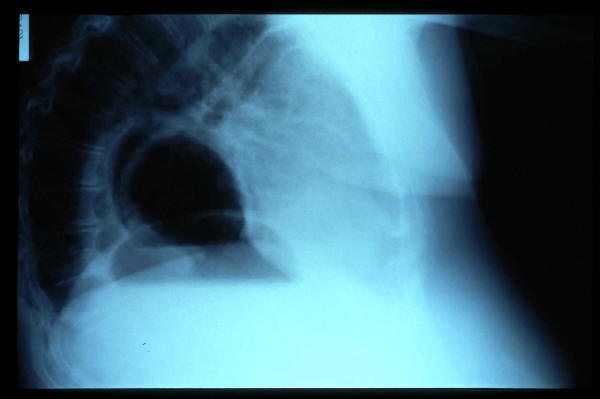

Fractura costal

Fractura costal por caída.

Paquipleuritis. Fractura costal.